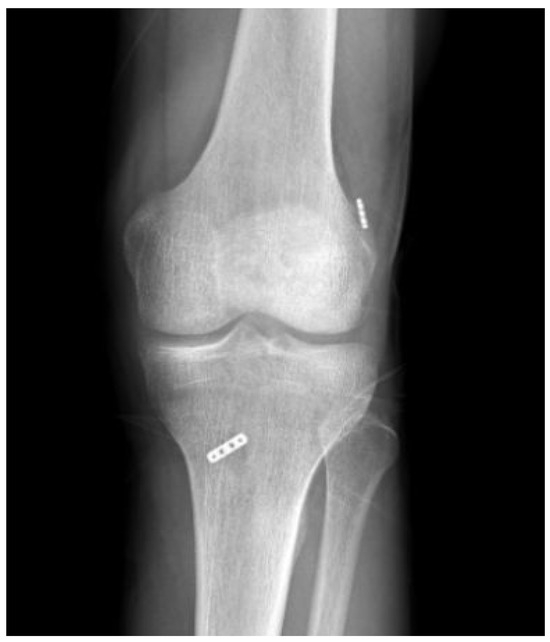

Does Rotation and Anterior Translation Persist as Residual Instability in the Knee after Anterior Cruciate Ligament Reconstruction? (Evaluation of Coronal Lateral Collateral Ligament Sign, Tibial Rotation, and Translation Measurements in Postoperative MRI)

2.1. MRI Evaluation Methods

2.5. Statistical Analysis